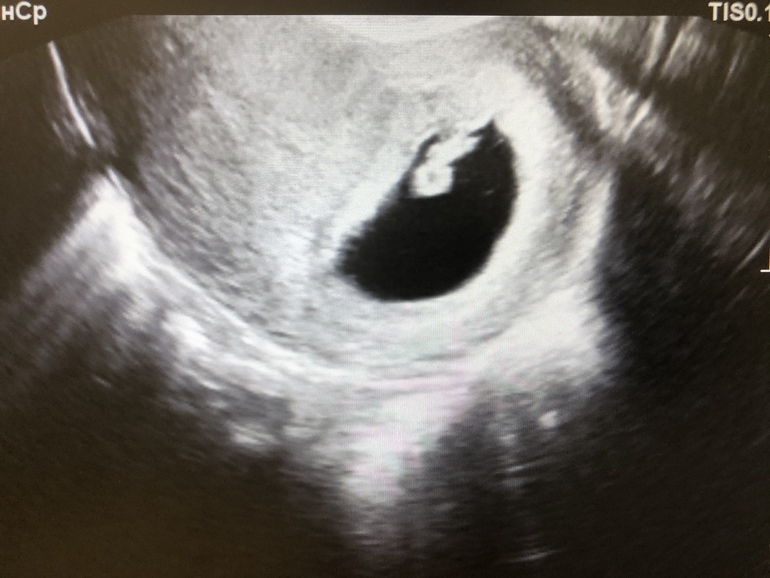

По УЗИ, по анализам и росту ХГЧ все В НОРМЕ! На фотографии УЗИ сегодняшнее, сердцебиение у эмбриона хорошее.